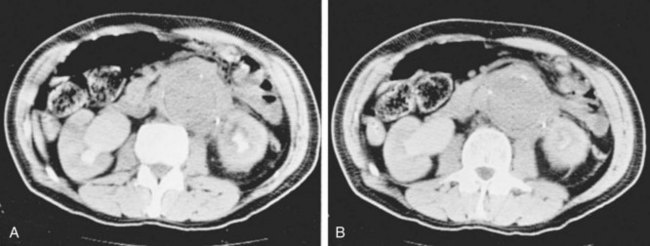

Currently, CT scanning is most frequently used to evaluate patients with an AAA that may demonstrate associated hydronephrosis (Fig. 40–16A and B). Ureteral findings associated with AAA vary. The ureters may be pushed laterally on both sides, or one side may deviate laterally while the opposite side is drawn medially within the perianeurysmal inflammation, or both may be medially deviated. Some have noted that lateral deviation of the ureter with AAA is usually not associated with obstruction (Labardini and Ratliff, 1967). The medial deviation of the ureter associated with the desmoplastic reaction of inflammatory aneurysms (IAAA), however, carries a more significant risk of ureteral obstruction. Although IAAA represents only between 4% and 15% of AAAs, the associated retroperitoneal desmoplastic reaction significantly increases the risk of ureteral obstruction, which has been reported in 21% of this cohort (Pennell et al, 1985; Arroyo et al, 2003).

Figure 40–16 A and B, Computed tomography scans demonstrate extensive retroperitoneal fibrosis associated with aneurysm of the abdominal aorta.

At one time, ureterolysis was routinely performed during repair of IAAA associated with ureteral obstruction. However, this practice has generally been abandoned, because obstruction commonly resolves without ureterolysis. Placement of internalized ureteral stents is commonly undertaken prior to IAAA repair. Ureteral obstruction has been reported to resolve in 80% of patients managed with this approach (Arroyo et al, 2003). Some have advocated endovascular repair of the IAAA in this setting (Nevelsteen et al, 1999). Internalized ureteral stents are inserted prior to endovascular graft placement and are removed when it is thought that the associated fibrosis has resolved. A 50% resolution of ureteral obstruction has been reported with this approach, while less favorable results have been demonstrated by others (Rehring et al, 2001; Deleersnijder et al, 2002; van Bommel et al, 2008). In a systematic review of endovascular repair of IAAA it was associated with persistent periaortic fibrosis leading to significant ureteral obstruction. Patients with IAAA treated with open surgery or an endovascular approach warrant close monitoring for development of recurrent or de novo ureteral obstruction, because delayed ureteral obstruction has been reported to occur (Simons et al, 2002; Jetty and Barber, 2004; Lambie et al, 2004).